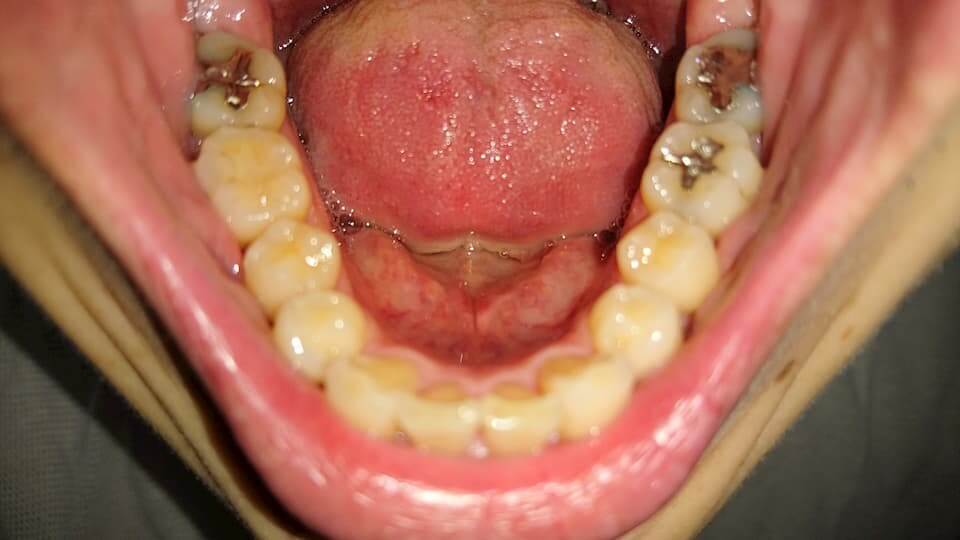

歯の写真